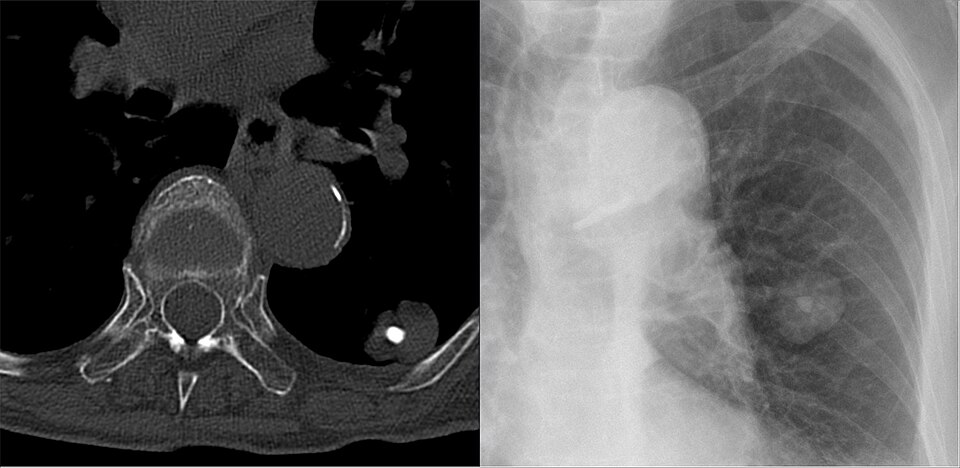

Лекарите често откриват хамартоми по време на образна диагностика поради други оплаквания от друго заболяване. Пациентите обикновено се нуждаят от допълнителни образни изследвания, за да потвърдят диагнозата.

Изображение: Hellerhoff, CC BY-SA 4.0, via Wikimedia Commons

Образните изследвания, от които може да се нуждаят пациентите, включват:

За потвърждаване понякога може да се наложи извършването на биопсия, ако лекарят не е сигурен, че образуванието не е злокачествено. Отстранява се част от тъканта, която се изпраща в лаборатория за хистологичен анализ.